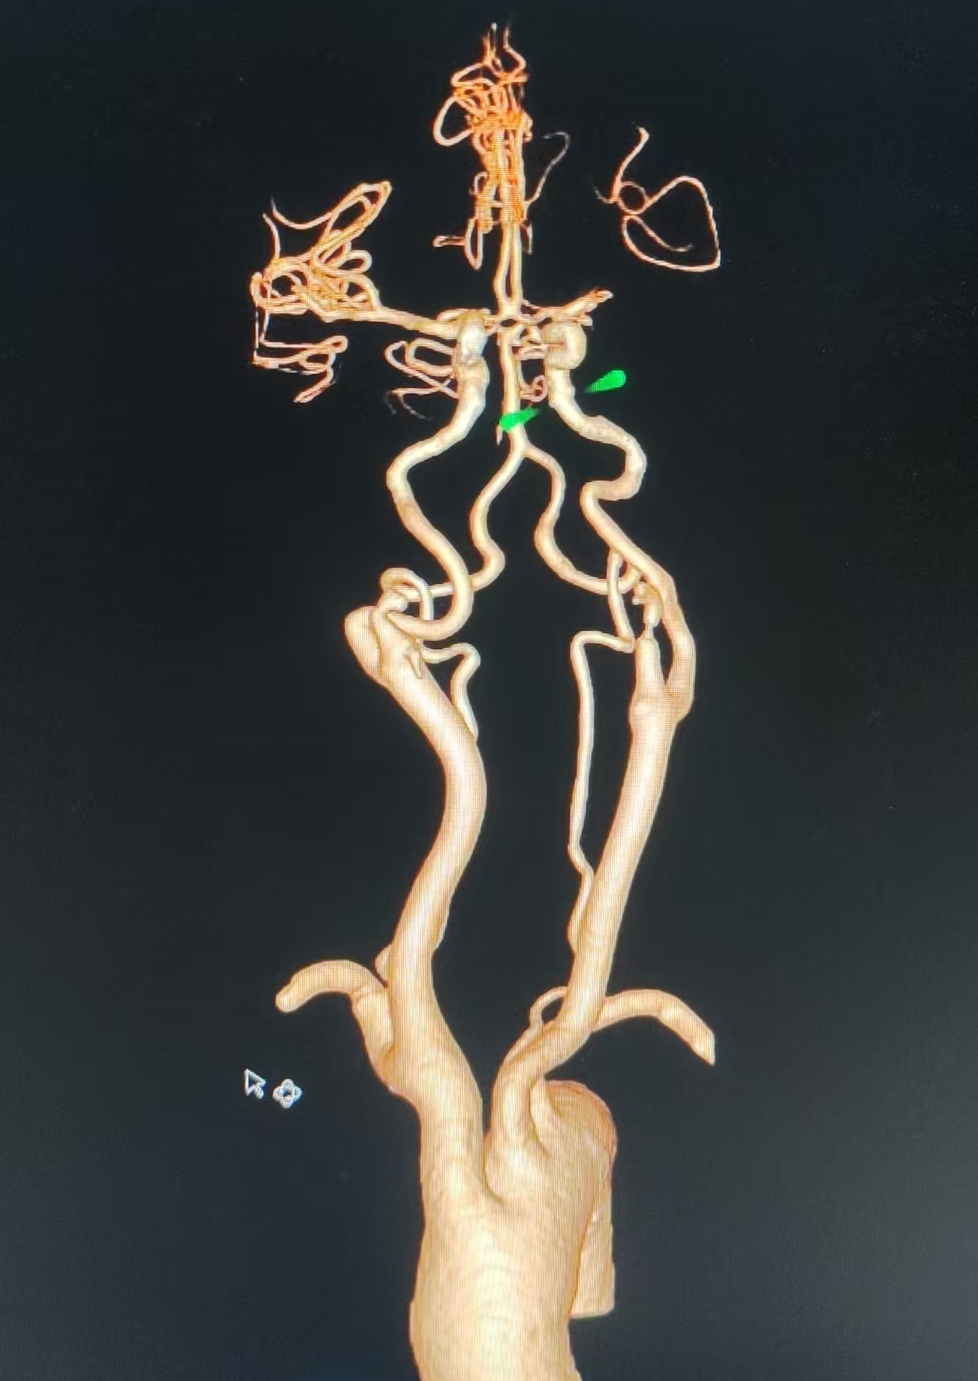

CTA提示左侧大脑中动脉闭塞

弓上造影:II型弓,大脑中动脉栓塞。

1.左侧大脑中动脉闭塞

房颤栓塞致左侧大脑中动脉闭塞。